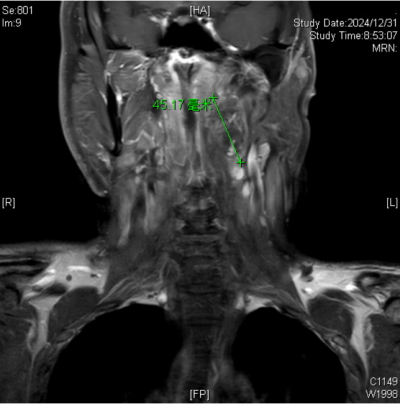

)的耳鼻咽喉头颈外科就诊。接诊的杨中纯副主任医师通过颈部增强磁共振成像(MRI)检查,最终确诊导致王永元咽部不适的罪魁祸首竟是咽旁后间隙肿瘤,紧邻口咽部。入院后,经过颈部CTA检查,发现肿瘤将颈内动脉推挤至外侧、变形,经过仔细阅片和详细的术前讨论,耳鼻咽喉头颈外科的医生团队制定了周密的手术计划。

颈部增强磁共振成像(MRI)下发现导致王永元咽部不适的罪魁祸首是咽旁后间隙肿瘤